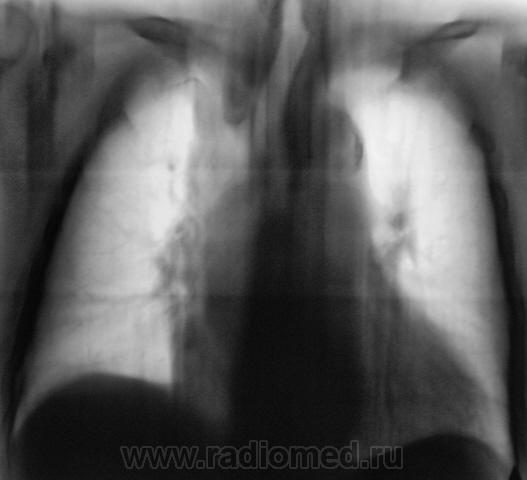

Контроль после флюорографии 3.

Пациентка взята на контроль после флюорографии. Произведено стандартное дообследование.